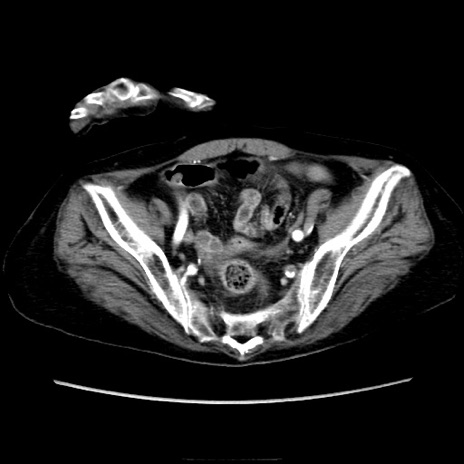

症例40(横断像)

【症例】90歳代女性

【主訴】腹痛・嘔吐

【現病歴】 食欲低下、嘔吐があり昨日他院受診。肺炎と診断され入院となる。入院後より腹部全体に圧痛あり。胃管留置され経過みていたが、症状持続するため、

当院転院となる。

【既往歴】胸椎圧迫骨折、胆石症

【身体所見】腹部:中央に激痛あり、圧痛あり、反跳痛不明

【データ】WBC 17100、CRP 18.82

横断像